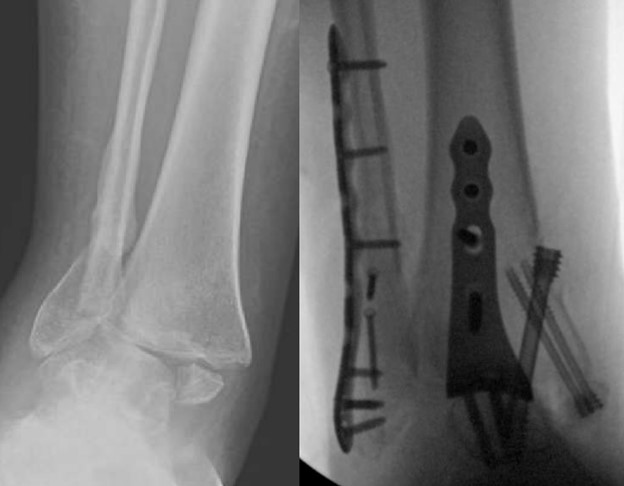

Led by Dr. Vinod Panchbhavi, a world-renowned orthopaedic foot and ankle surgeon, our fellowship covers all aspects of foot and ankle surgery including trauma, reconstruction, ligament and tendon injuries, arthroscopy, arthroplasty, and midfoot and

education. While he practices all aspects of foot and ankle surgery, he has made especially significant contributions in advancing our understanding of charcot arthropathy and Lisfranc injuries.

where he performed around 100 cases of total ankle arthroplasty. His other clinical interests include minimally invasive surgery and foot and ankle trauma.

- Clinical exposure: Between the three attendings, you will have between 500-800 cases for the year, covering all aspects of foot and ankle surgery. Each attending has his own operating style and have different backgrounds so you will be exposed to

a variety of techniques and methods. In addition, UTMB provides medical care to the Texas Department of Criminal Justice, which allows for exposure to some of the most complex pathology possible. Finally, the fellowship is very hands-on and graduated

autonomy is given early and often.